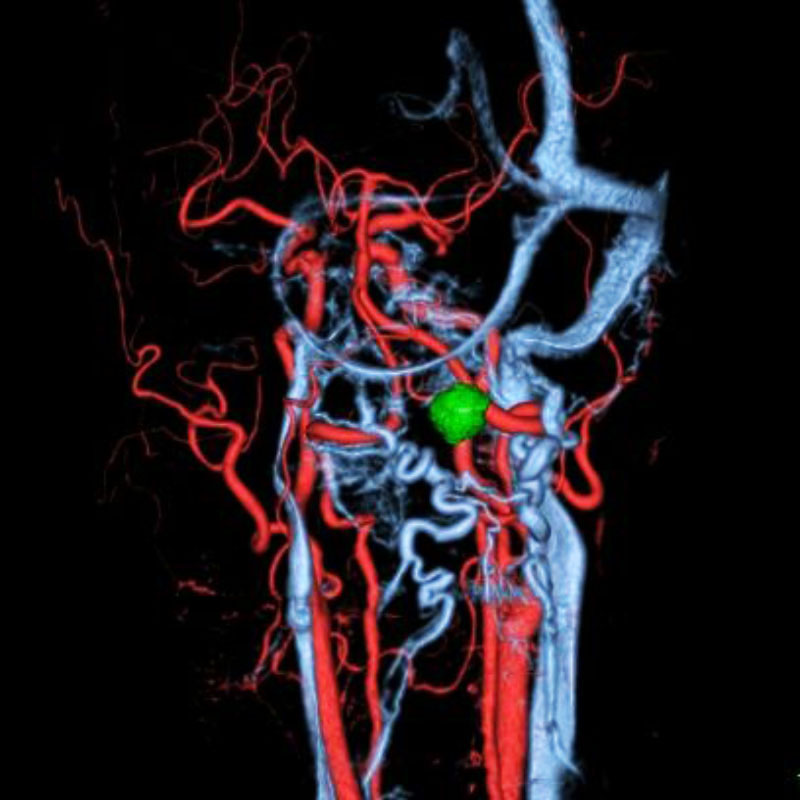

脳動静脈奇形

血管塞栓術

芝野/古谷

脳動脈瘤(Acom)

脳血管内手術

芝野/古谷/木本